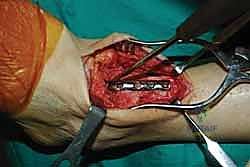

- رؤية ممتازة للمفصل: يوفر المدخل الأمامي رؤية بانورامية واسعة ومباشرة لكامل السطح المفصلي للظنبوب وعظم الكاحل، مما يسمح بإزالة الغضاريف التالفة بدقة متناهية.

- تصحيح التشوهات بدقة: يسمح هذا المدخل بتعديل انحرافات الكاحل (سواء كان يميل للداخل Varus أو للخارج Valgus) وإعادته إلى المحور الميكانيكي الطبيعي للساق.

- الحفاظ على عظم الشظية (Fibula): على عكس المدخل الجانبي الذي يتطلب غالباً قطع عظم الشظية، يحافظ المدخل الأمامي على الشظية سليمة، مما يحافظ على العرض الطبيعي للكاحل ويحمي الأربطة الجانبية.

- تثبيت ميكانيكي حيوي أقوى: يتيح المدخل الأمامي وضع شريحة معدنية (Anterior Plate) على الجانب الأمامي للمفصل. من الناحية الميكانيكية الحيوية (Biomechanics)، يعتبر الجانب الأمامي هو "جانب الشد" (Tension side) أثناء المشي. وضع الشريحة هنا يوفر تثبيتاً فائق القوة ويقلل من معدلات عدم الالتئام.

خطوات جراحة تثبيت مفصل الكاحل الأمامي بالتفصيل (Step-by-Step Surgical Procedure)

1. الوضعية والشق الجراحي (Positioning and Incision)

يستلقي المريض على ظهره (Supine position). يتم استخدام عاصبة (Tourniquet) حول الفخذ لتقليل النزيف وتوفير رؤية واضحة. يقوم الدكتور هطيف بإجراء شق طولي أمامي فوق مفصل الكاحل، عادة بين وتر العضلة الظنبوبية الأمامية (Tibialis Anterior) ووتر العضلة الباسطة الطويلة لإصبع القدم